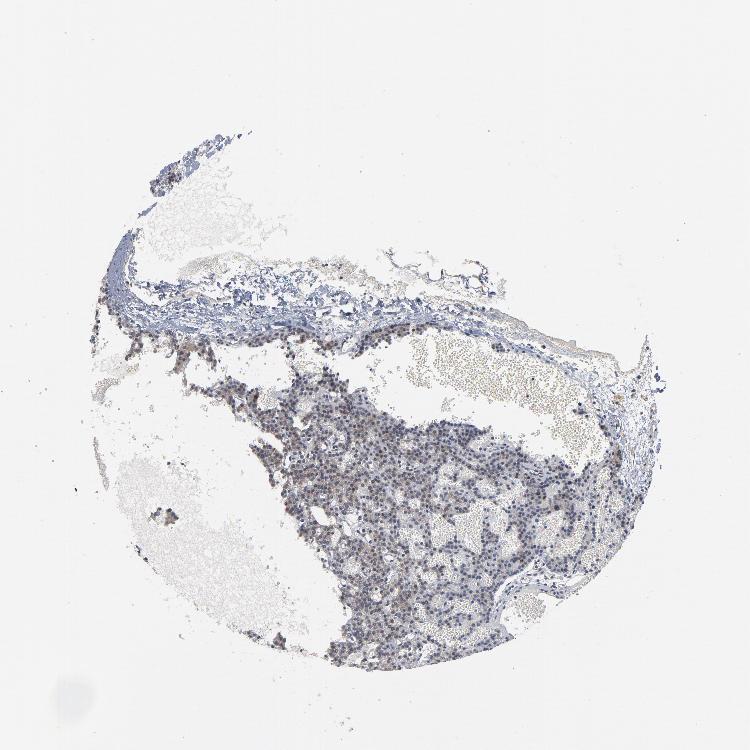

TISSUE PRIMARY DATA PARATHYROID GLAND Show tissue menu

PARATHYROID GLAND - Antibody stainingi

Antibody staining in the annotated cell types in the current human tissue is reported as not detected, low, medium, or high, based on conventional immunohistochemistry profiling in selected tissues. This score is based on the combination of the staining intensity and fraction of stained cells.

Each image is clickable and will lead to virtual microscopy that enables deeper exploration of all samples and also displays staining intensity scores, fraction scores and subcellular localization as well as patient and tissue information for each sample.

Antibody HPA048630Antibody HPA061142Antibody CAB004026

Glandular cells LowNot detectedLow